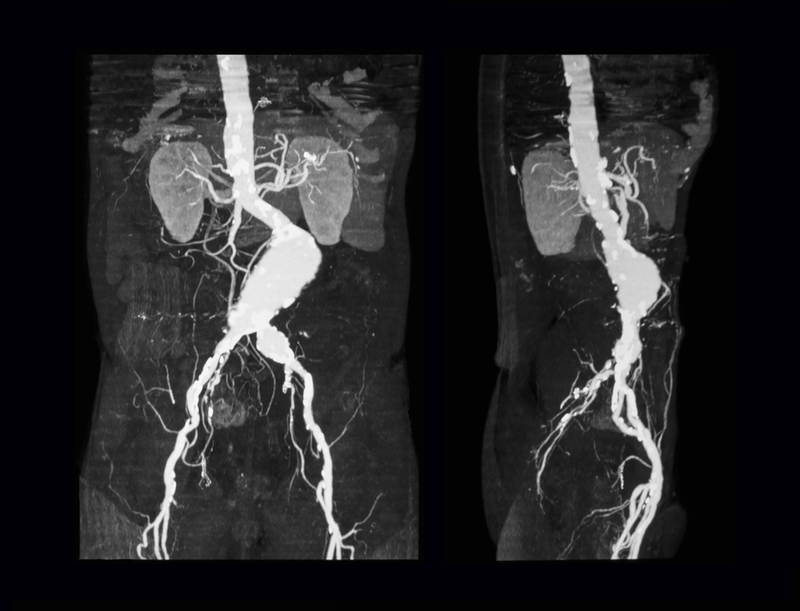

A 50-year-old farmer’s life-threatening condition was discovered just in time when he came to KIMS from a village near Guntur with pain in the abdomen. Upon investigation, his scans showed that he had bulge of vessel measuring 9 centimeters from the chest to the abdominal aorta. A challenging 16-hour hybrid surgery was successfully performed by team of vascular surgeons led by Dr Narendranadh Meda and Dr Chandrasekhar in co-ordination with anesthesia team.

Speaking on the occasion, Dr Meda, Vascular and Endovascular surgeon, an expert in aortic-related diseases, said, “Patient was a known hypertensive, on investigation with CT, we found that he had a very large thoraco-abdominal aortic aneurysm (Main blood vessel carrying the blood from heart to the body) measuring nine centimeters in diameter was seen with impending rupture, involving the arteries supplying the bowel and kidneys.

Generally, Aneurysms greater than five centimeters are considered dangerous and need treatment.” His condition required an extensive surgery and we have opted for open De-branching (reconnecting all blood vessels) bypass surgery to replace portions for two visceral vessels which supply liver, bowel and two renal vessels and supply kidneys with a Dacron woven graft with reversing supply from normal infrarenal aorta, he said.

Once the blood supply to the visceral and renal arteries was secured a stent was placed in the same setting to exclude the aneurysmal segment,” he added. It took 16-hours for us to complete the surgery, Dr Meda said. People suffering from such advanced Aortic Aneurysm should have an early diagnosis made, he cautioned. In most cases, abdominal aortic aneurysms cause no symptoms and are found when being evaluated for another medical condition. If there is a family history of aneurysm and feel sudden severe pain in abdomen or back, one should seek immediate care.